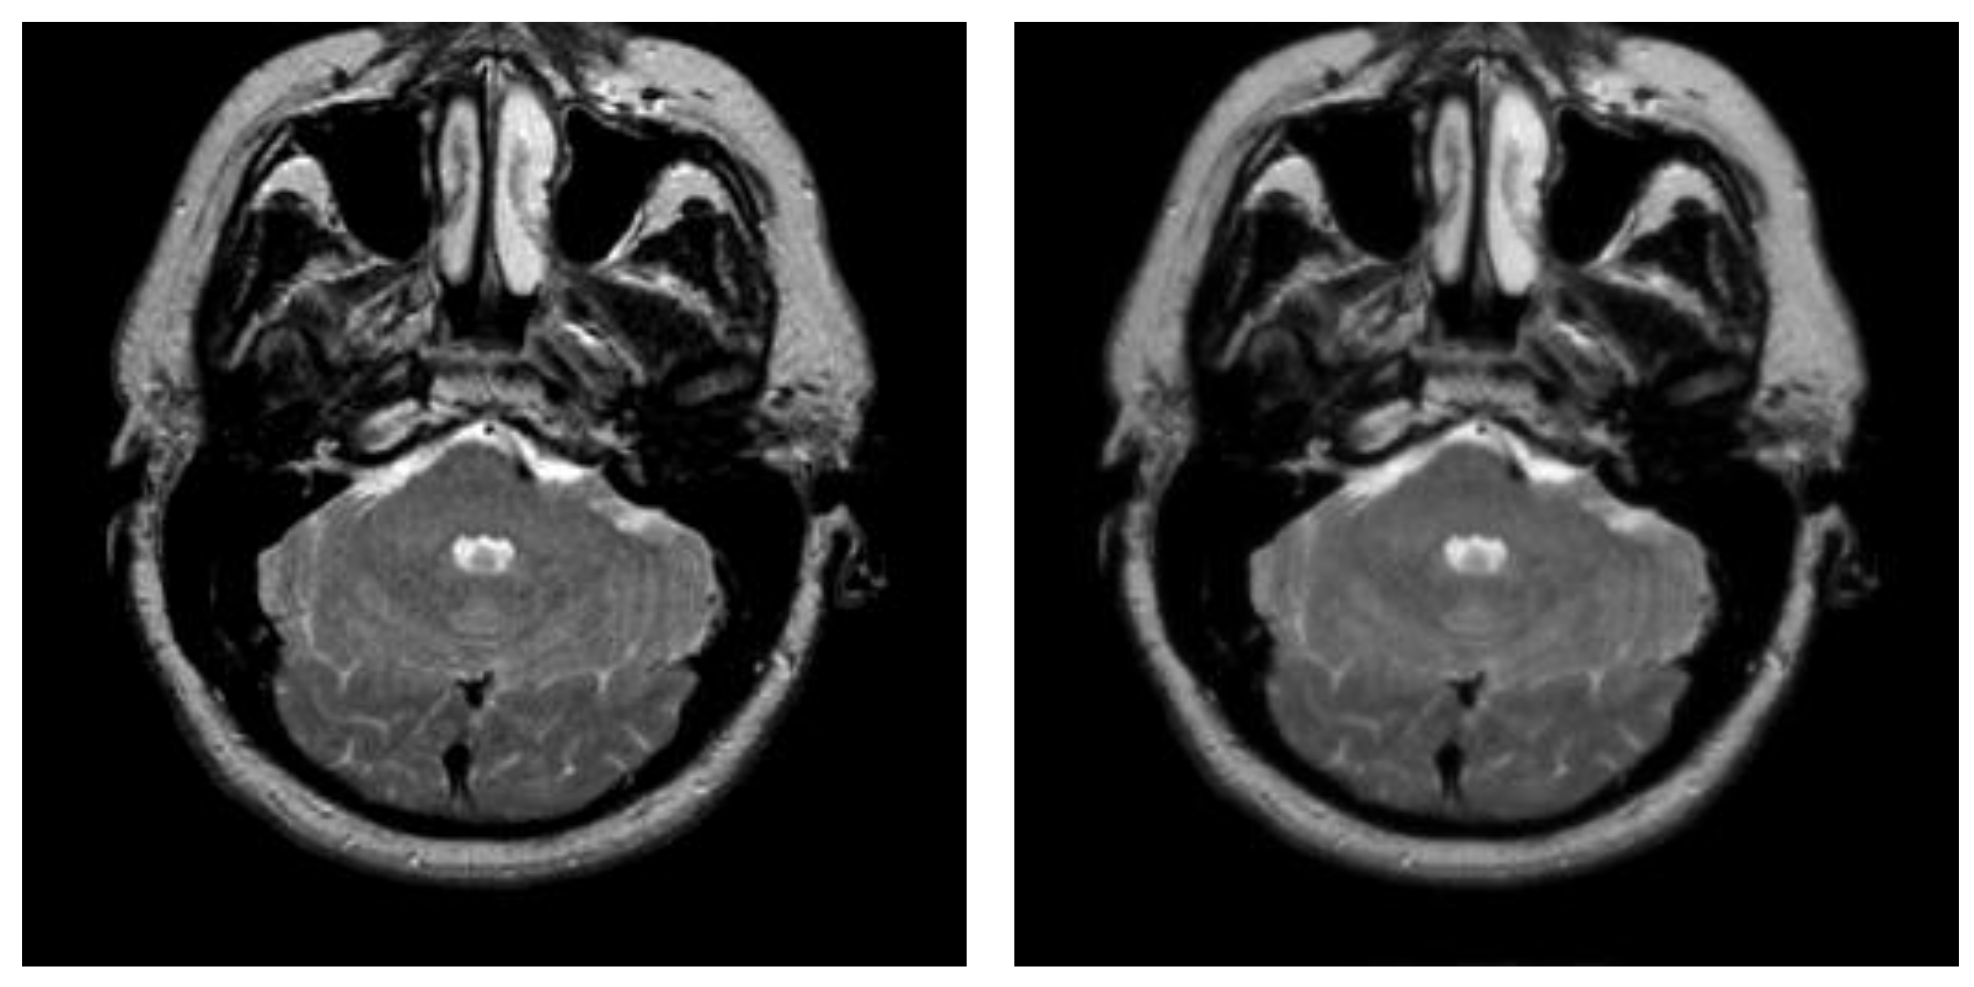

In this subsection, we applied the proposed algorithm to the BRATS (Multimodal Brain Tumor Image Segmentation Benchmark) database. The BRATS database (http://www.imm.dtu.dk/projects/BRATS2012/data.html, accessed on 25 September 2021) is compiled from the international brain tumor segmentation challenge in MICCAI 2012 conference. It is a widely used database and composed of multi-contrast brain MR scans of 25 low-grade and 25 high-grade glioma cases and the corresponding ground truth. Each case includes four modalities—T1, T1c, T2, and FLAIR [44]—and each MR scanning sequence contains more than one hundred images. Figure 20 presents an example of brain MR images from BRATS. Figure 20a shows the original images and the corresponding ground truth is displayed in Figure 20b.

Figure 20.

An example of original images and ground truth from BRATS: (a) original images, (b) ground truth.